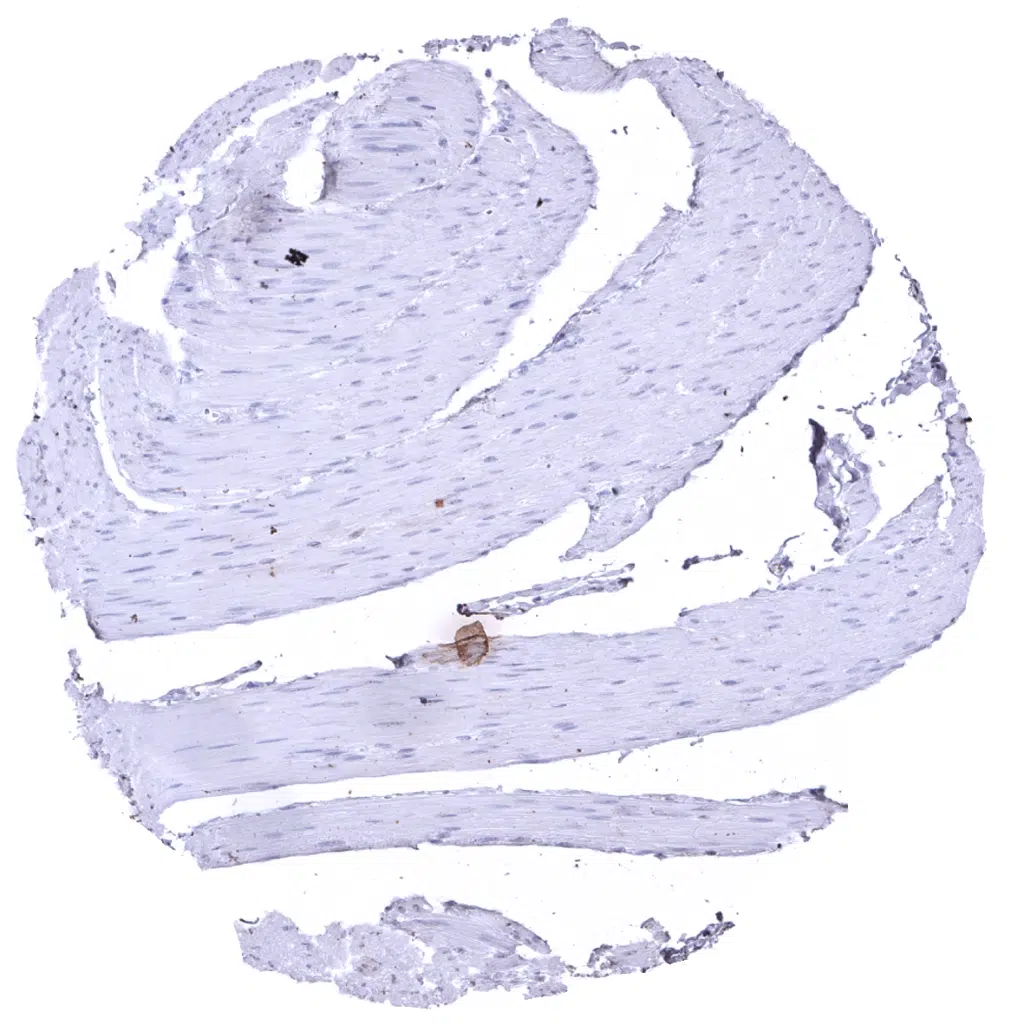

Uterus, myometrium - In the uterus, bundles of smooth muscle cells show weak to moderate pan Cytokeratin immunostaining.

Uterus, myometrium - pan Cytokeratin staining is not always seen in myometrium samples.